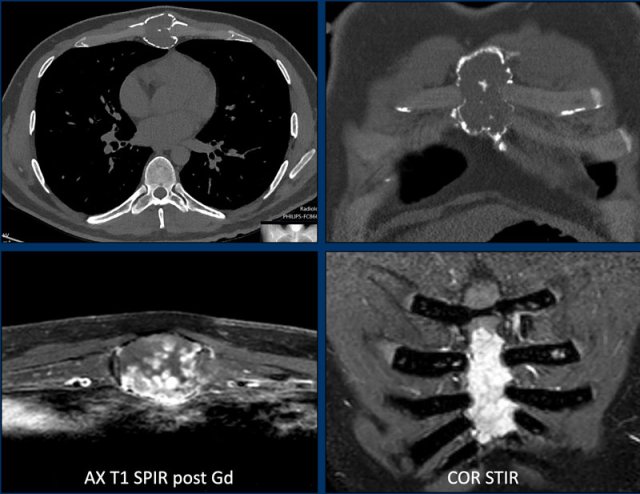

Case

Let’s continue with a chondroid tumor in the axial skeleton. We have to shift gears as there is a different approach than for lesions in the appendicular skeleton.

First look at the images.

Then continue reading.

Images

Axial CT shows an expansile

osteolytic tumor in the corpus of the sternum.

There are multiple foci of cortical

destruction.

Popcorn calcifications are present centrally.

MRI confirms the chondroid nature of

this tumor with hyperintense signal on the STIR-image and septonodular contrast

enhancement.

Conclusion

Although there is no soft

tissue component, due to the expansion and multiple foci of cortex destruction this tumor should be called a chondrosarcoma of grade II or higher and en bloc resection

is the correct treatment.

Pathology showed a grade II chondrosarcoma.

In the axial skeleton chondroid tumors have a worse outcome.

This implies, that they are resected even if they are grade I as opposed to the same tumor in the appendicular skeleton, which is called an ACT and will receive follow up.

Do not call axial tumors enchondromas if they show cortical scalloping or cortical destruction, as this would lead to undertreatment.

In cartilage tumors, perfusion has been used to differentiate enchondroma from chondrosarcomas.

A cut off of 10 seconds is used for fast versus slow enhancement. However, overlap in early enhancement patterns of CS and enchondroma may occur, for example: fast enhancing enchondromas exist, but also slow enhancing ACTs.

Example of a slow enhancing ACT (orange line), more than 10 seconds after the artery (blue line).

A chondroid tumor in the sternum with perilesional oedema and septonodular enhancement.

The perfusion images show fast enhancement of the tumor (orange ROI and curve) , within 8 seconds after the aorta (blue ROI and curve).

The pink ROI and curve represent mucoid which does not enhance.

This lesion was resected.

Final diagnosis: CS-I in the sternum